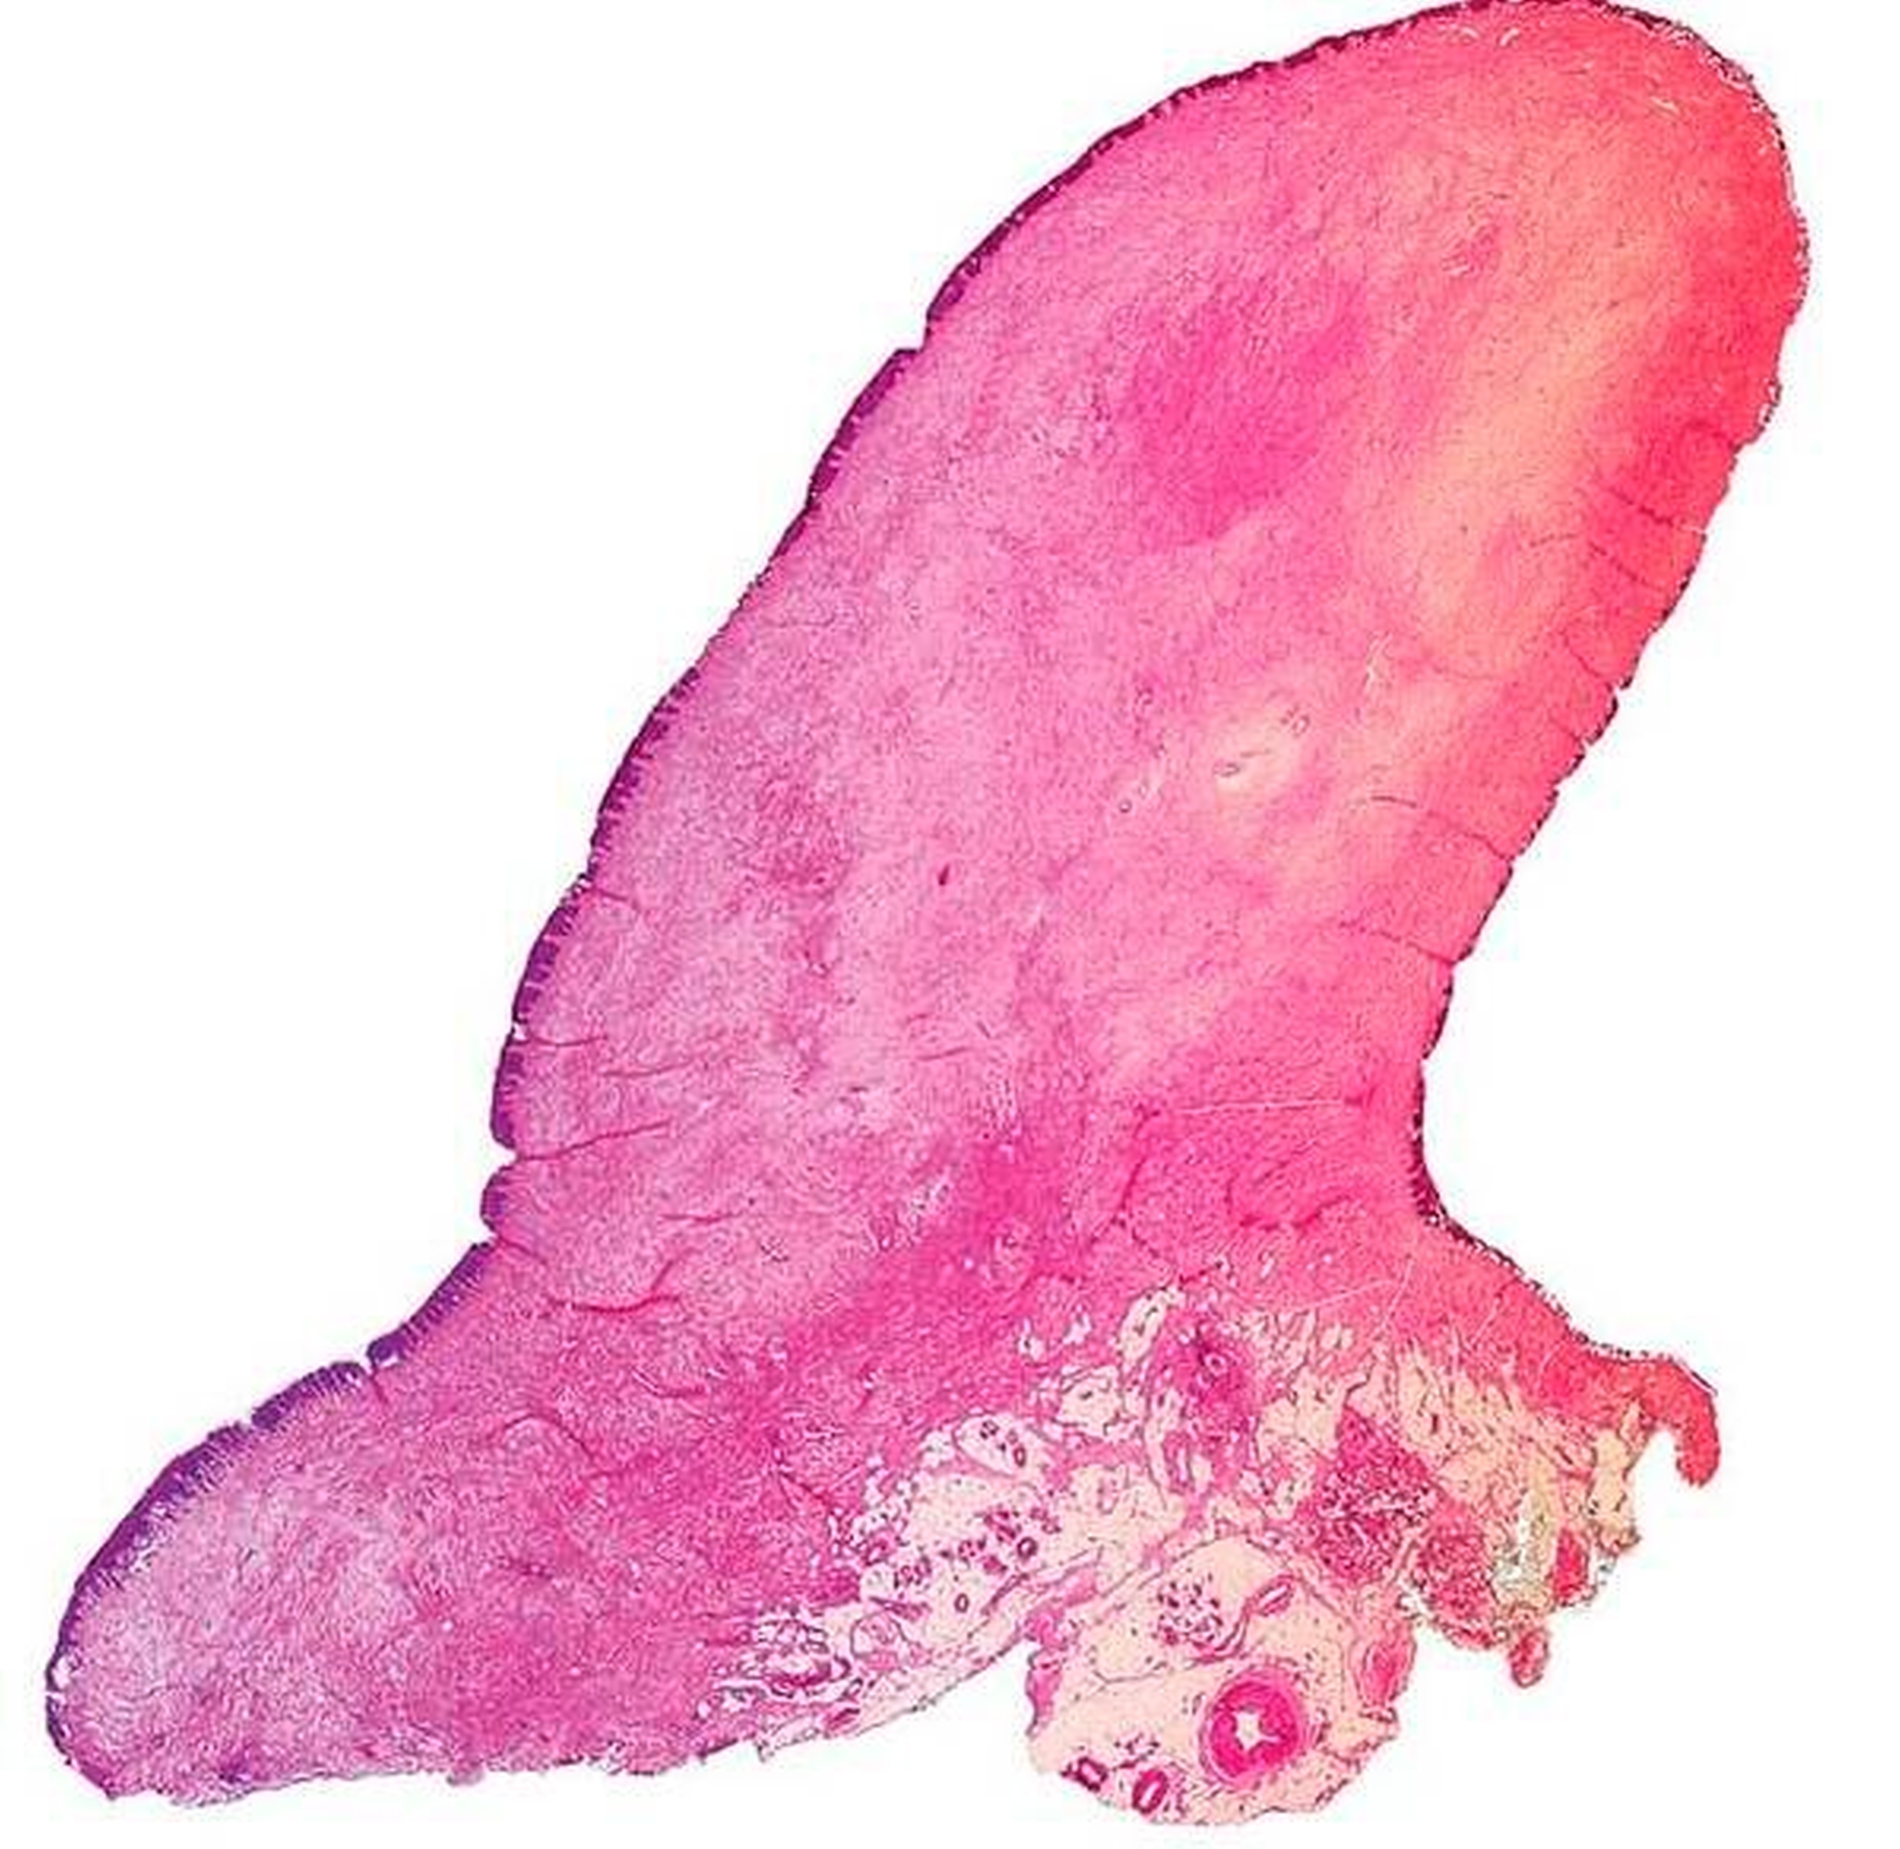

Nach Auswertung des Bildmaterials und Vervollständigung der präoperativen Aufklärungen konnte die Exzision des Befunds problemlos unter ambulanten Bedingungen in Intubationsnarkose durchgeführt werden (Abbildung 1 rechts und Abbildung 3).

Die histopathologische Nachuntersuchung des Gewebeexzidats ergab den Befund eines echten polypösen Schleimhautfibroms ohne Anhalt für Malignität (Abbildungen 4a und 4b). Während der klinischen Nachsorge zeigte sich die per secundam ablaufende Wundheilung unter Zuhilfenahme einer Verbandsplatte und der täglichen Anwendung von 0,12-prozentiger Chlorhexidin-Mundspüllösung unter weiter bestehender immunsuppressiver Medikation und starkem Nikotinabusus zwar zeitverzögert, aber insgesamt unauffällig (Abbildung 5).